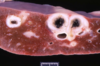

A 3 week-old foal died unexpectantly. On post-mortem examination the brain exhibited the following changes. What is the process occurring in the images?

A

Liquefactive necrosis